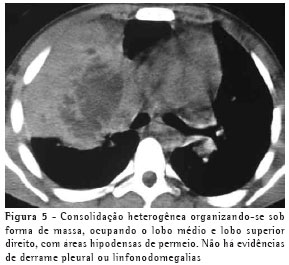

O achado de imagem mais freqüente, presente nos 7 pacientes, foi consolidação de contornos mal definidos (Figuras 1, 2, 3 e 4), sendo que 5 deles tinham broncograma aéreo de permeio, principalmente na periferia da lesão. Em 3 casos, a consolidação organizava-se sob forma de massa. Em 6 dos 7 pacientes foram observadas, no interior das consolidações, áreas irregulares de escavação, múltiplas em 5 e única em 1 paciente. Em um dos casos não se observou escavação, mas ele mostrava áreas hipodensas de permeio, sugestivas de necrose (Figura 5). Apenas um dos pacientes apresentou nível líquido no interior das cavidades.

Na nossa casuística, o principal padrão de acometimento pulmonar foi o de consolidação com broncograma aéreo de permeio e escavação, presente em 6 pacientes, sendo as escavações múltiplas em 5 casos e única em 1. As consolidações tinham grandes proporções e contornos anfractuosos. Os broncogramas aéreos estavam localizados nas porções periféricas das lesões. O lobo pulmonar mais freqüentemente envolvido foi o lobo superior direito, acometido em 4 pacientes. A maioria dos trabalhos de revisão de casos confirma tais achados.(2,5) Alguns trabalhos relatam que, embora a escavação possa não estar presente no momento do diagnóstico, ela acaba por se desenvolver durante a evolução da doença.(4) Níveis líquidos no interior das escavações foram vistos em apenas um paciente na casuística estudada.